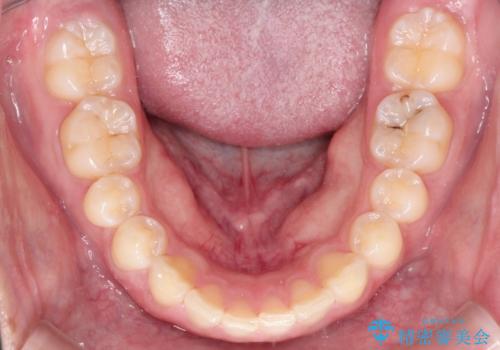

上の歯が全体的に下の歯の位置に比べると前方に位置しており、上の前歯が前方に傾斜している状態でした。

上の奥歯を後方に移動して、隙間を作り、前歯を引っ込める計画としました。